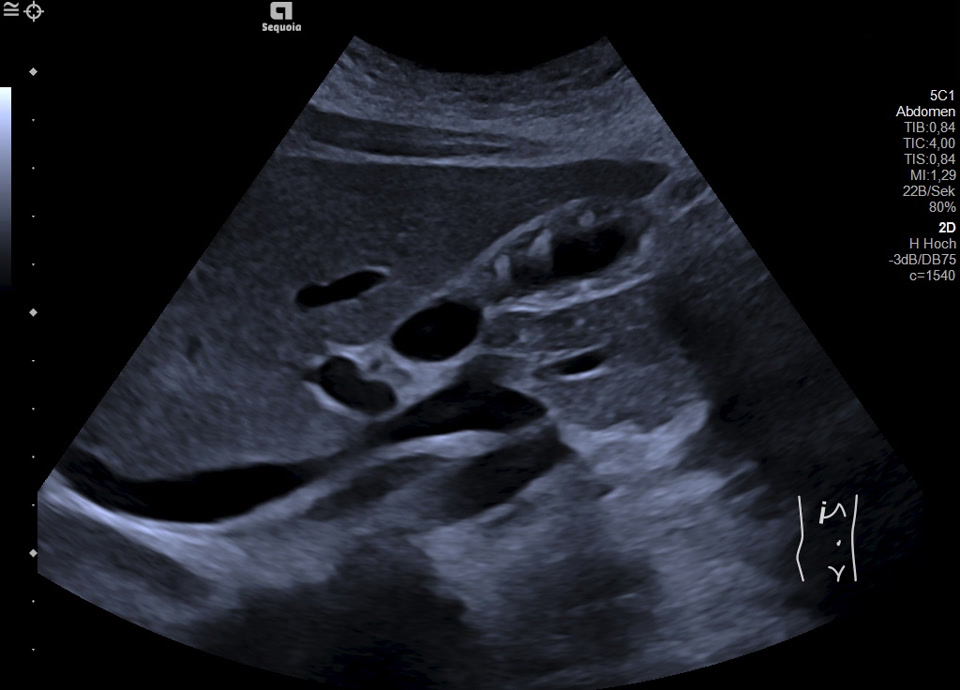

16-jährige Patientin berichtet seit mehreren Monaten über rezidivierende Durchfälle und Bauchschmerzen im Bereich der rechten Colonflexur, zuletzt etwa alle 14 Tage. Vor zwei Monaten wurde sie nach einer besonders starken Episode in die Klinik überwiesen; Labor unauffällig. Zum Zeitpunkt der letzten Untersuchung beschwerdefrei. Sonographisch zeigt sich eine Wandverdickung der Gallenblase mit inhomogener Schichtung bei erhaltener, glatter Innen- und Außenkontur. Betroffen sind vor allem Fundus und Corpus, das Infundibulum erscheint unauffällig. In den verdickten Wandabschnitten finden sich hyperechogene Einzelechos mit Reverberationsartefakten (Kometenschweifartefakte). Zusätzlich zeigen sich in der Hochfrequenzsonografie (Video) echofreie, kleinzystische Areale in der Wand, die den erweiterten Rokitansky-Aschoff Sinus entsprechen. Charakteristischer Befund einer segmentalen Gallenblasenadenomyomatose.